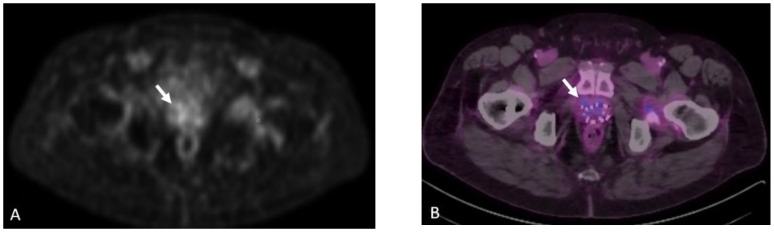

Figure 5.

Eighty-four-year-old male with elevated PSA levels. PET image shows increased uptake within the right lateral peripheral zone concerning for recurrence. Corresponding CT shows no abnormality in the area of pathology. Magnetic resonance imaging (MRI) Diffusion-Weighted-Imaging (DWI), (A) sequence through the prostate shows increased DWI signal in the right mid-gland (arrow), PiRads 5. NECT (B) shows no discernable abnormality in the area of interest; however, corresponding Axumin PET (C) shows intense Axumin uptake (arrow).